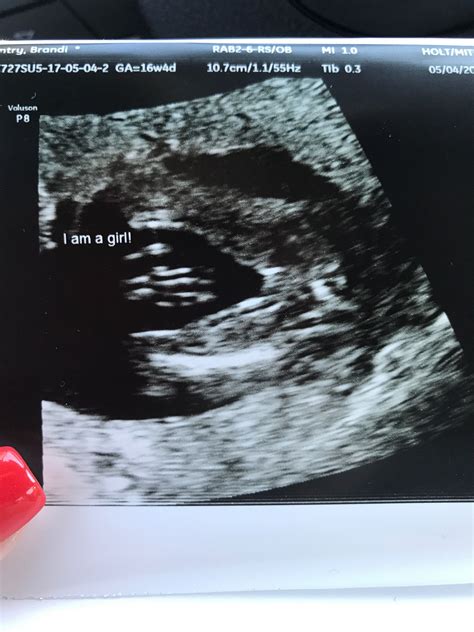

16 Weeks Pregnant Ultrasound

At 16 workweek, you are formally in your quaternary month of pregnancy. Your baby is grow rapidly, and your body is undergoing numerous alteration to back this growth. This workweek is oft tag by a routine prenatal check-up, which may include a 16 weeks meaning ultrasound. This echography is typically perform to value your baby's ontogeny and to insure for any likely matter.

At 16 week, you are well on your way to welcome your little one into the world. The 16 weeks significant ultrasound is a important milepost that provides valuable insights into your baby's growth and overall health. Embracing this journeying with fervor and self-confidence, know that you are rear a new life with love and fear.